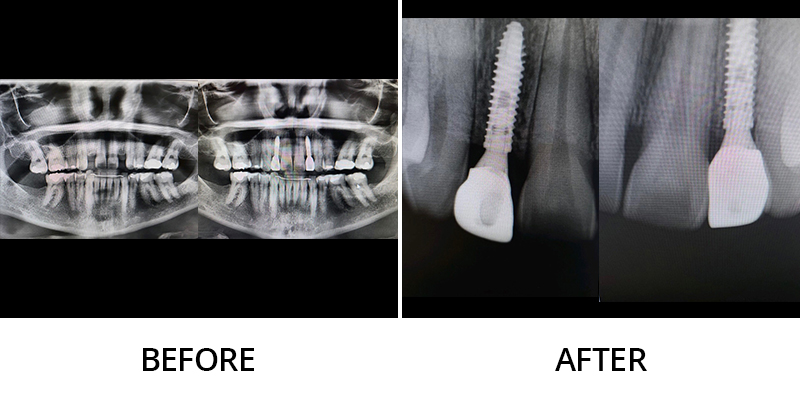

We invite you to explore this smile gallery page to see some of the beautiful results Dr. Kevin Grimm has helped his patients achieve. If you have questions about our dental services, or to schedule your personal consultation with our skilled dentist in Okemos, Michigan, please contact Okemos Smile Center today at (517) 349-3110. We look forward to helping you transform your smile!